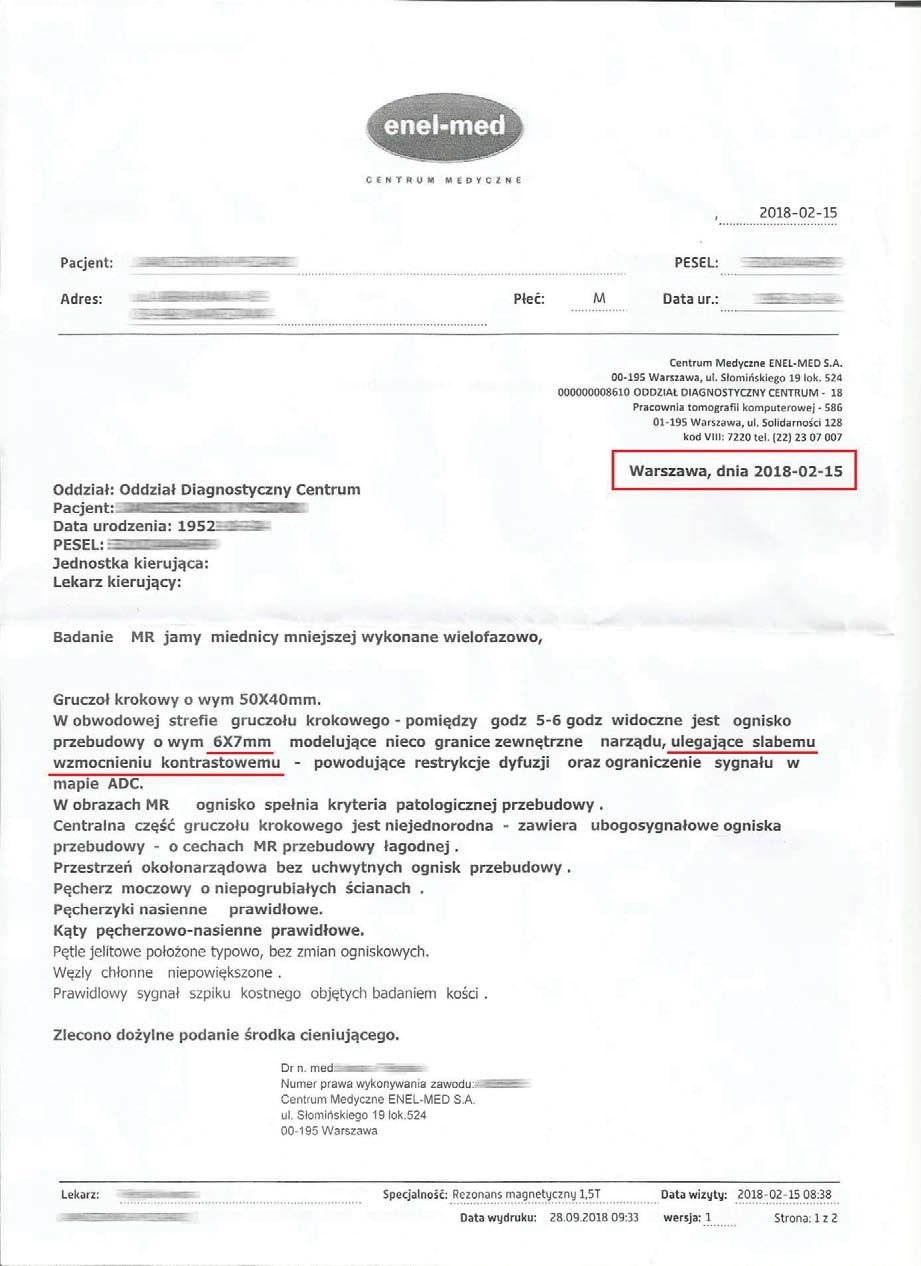

EFEKT PREPARATU NA GUZIE HYPOECHOGENNYM

Mężczyzna lat 66 z guzem hypoechogennym o wymiarach początkowych 16x10mm i wymiarach prostaty 55x47 mm zastosował terapię preparatem, a po 3 miesiącach zaobserwowano pierwsze zmiany w postaci zmniejszenia ogniska do wymiarów 6x7 mm a także zmniejszenie rozmiarów samej prostaty do 50x40 mm.

Badanie po 6 miesiącach stosowania preparatu wykazało brak guza- potwierdzone badaniem obrazowym, dodatkowo prostata zmniejszona do rozmiaru optymalnego (48x61mm), charakterystycznego dla grupy wiekowej. Pełny zanik guza w tak krótkim czasie bez ingerencji chemio i radioterapii wskazuje na głęboką regenerację komórkową. Preparat stymulując mitochondria dostarcza zwiększoną ilość mitochondrialnego ATP, dzięki któremu dochodzi do apoptozy uszkodzonych komórek prostaty. Proces regeneracji komórkowej poprzez stymulację i zabezpieczenie struktury i funkcji mitochondriów wycofuje niekontrolowany podział, co wskazuje na działanie antynowotworowe bez toksyczności.